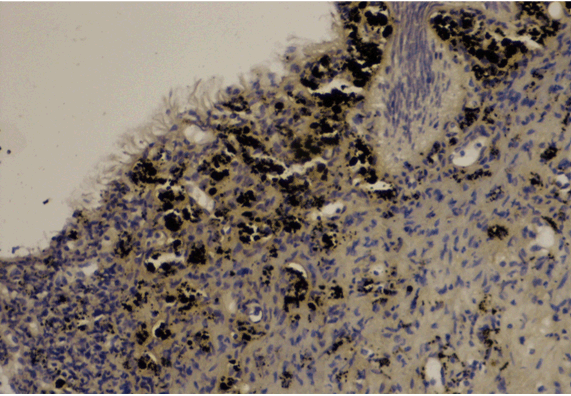

Bladder biopsy histologically revealed diffuse dark brown-black pigment mostly within the superficial lamina propria, focally in the overlying urothelium (Figure 4).

Figure 4: Diffuse dark brown-black pigment within the superficial lamina propria and focally involved the overlying urothelium (H&E stain, x100).